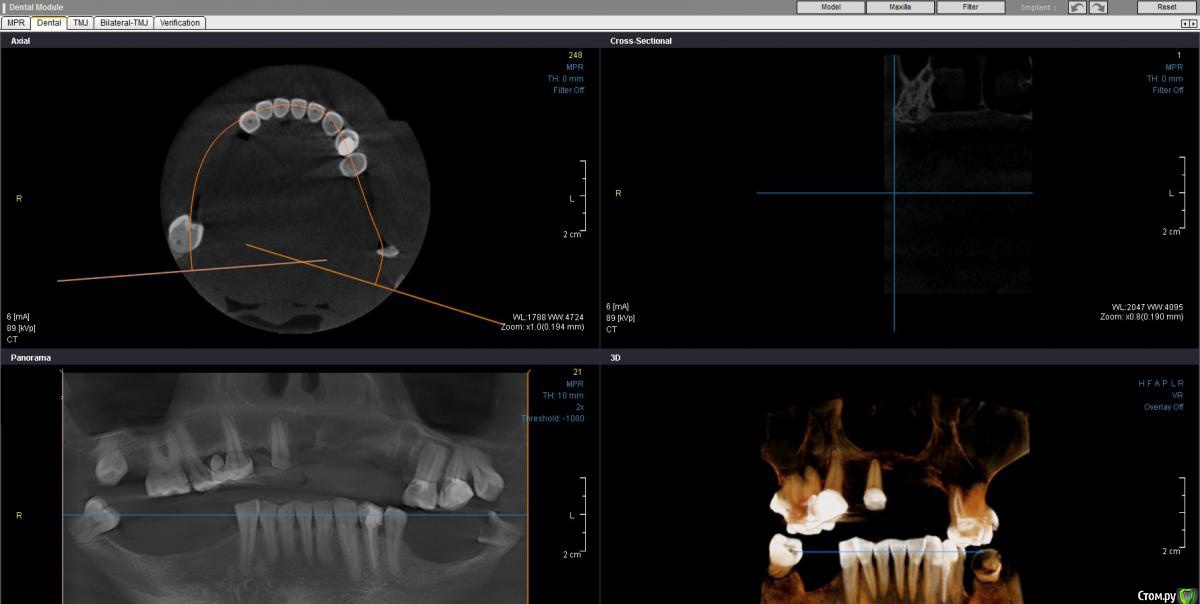

Здравствуйте! У мамы упал мост на верхней челюсти справа, пошла в поликлинику, сняли оставшийся мост слева, удалили 2 зуба, сказали, что нужно ставить частично-съемный протез (вроде бюгельный).

Отправили на 3д снимок, ортопед посмотрел, говорит удалять еще 2 зуба, кажется 8ки. Уважаемые доктора, что посоветуете, мама волнуется, что удалили зубы и еще предстоит. И все как-то затягивается, уже месяц "без зубов", еще предстоит около месяца.. С нижними тоже пока не ясно.